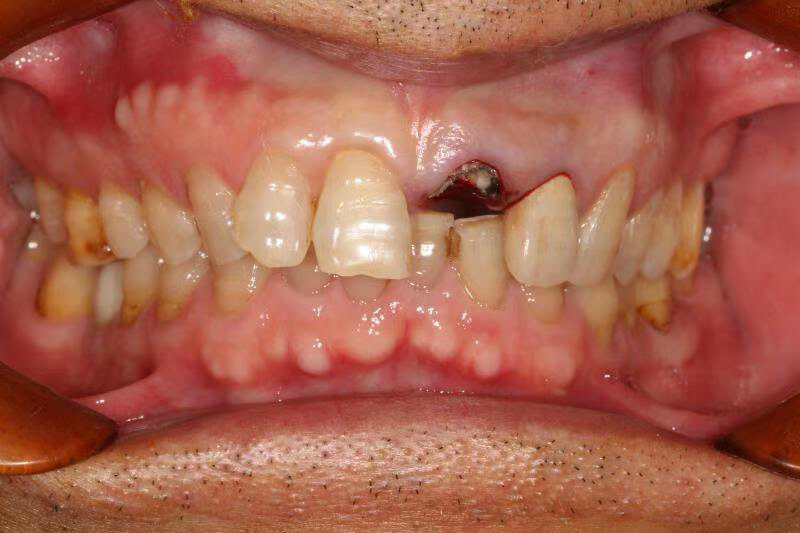

患者中年男性,左上中切牙外院烤瓷冠修复多年,因牙冠脱落前来就诊,由于牙冠制作不够密合,牙齿已经腐烂成残根,无法修复,只能进行种植修复,由于是门牙,我们在做完种植术后为患者制作了临时冠,最大程度保证了美观性。